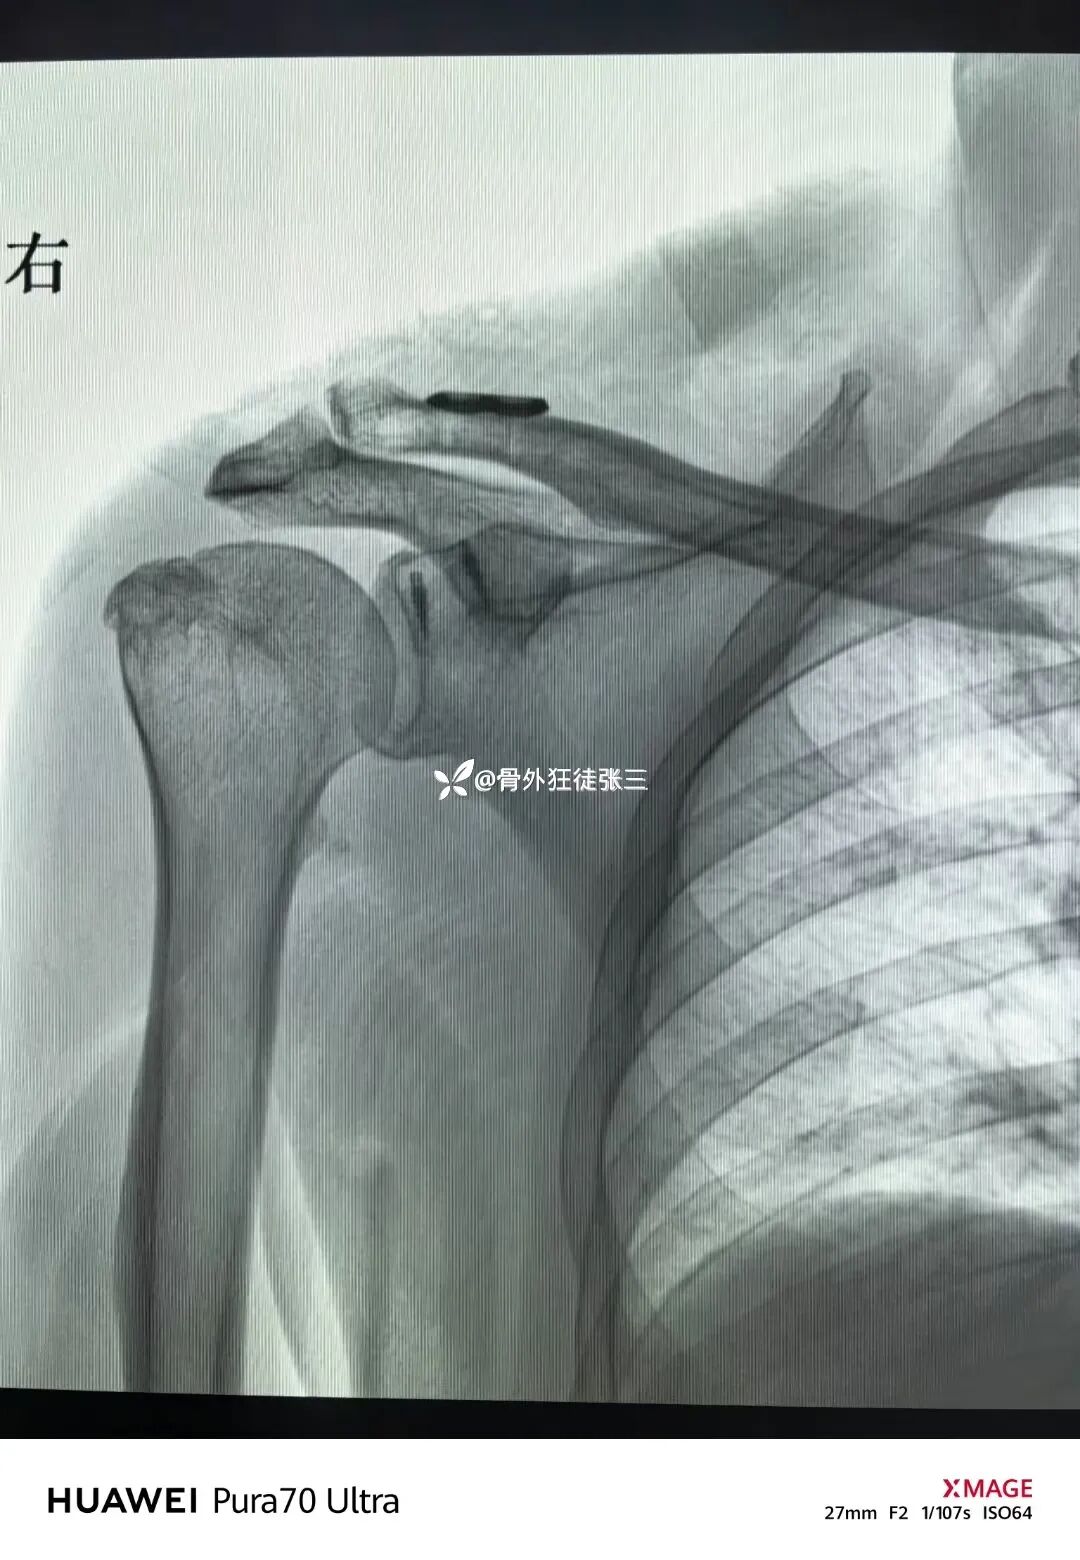

大清早还看到一个患者发的片子

袢板术后2天再脱位

当然和技术和患者依从性关系也很大